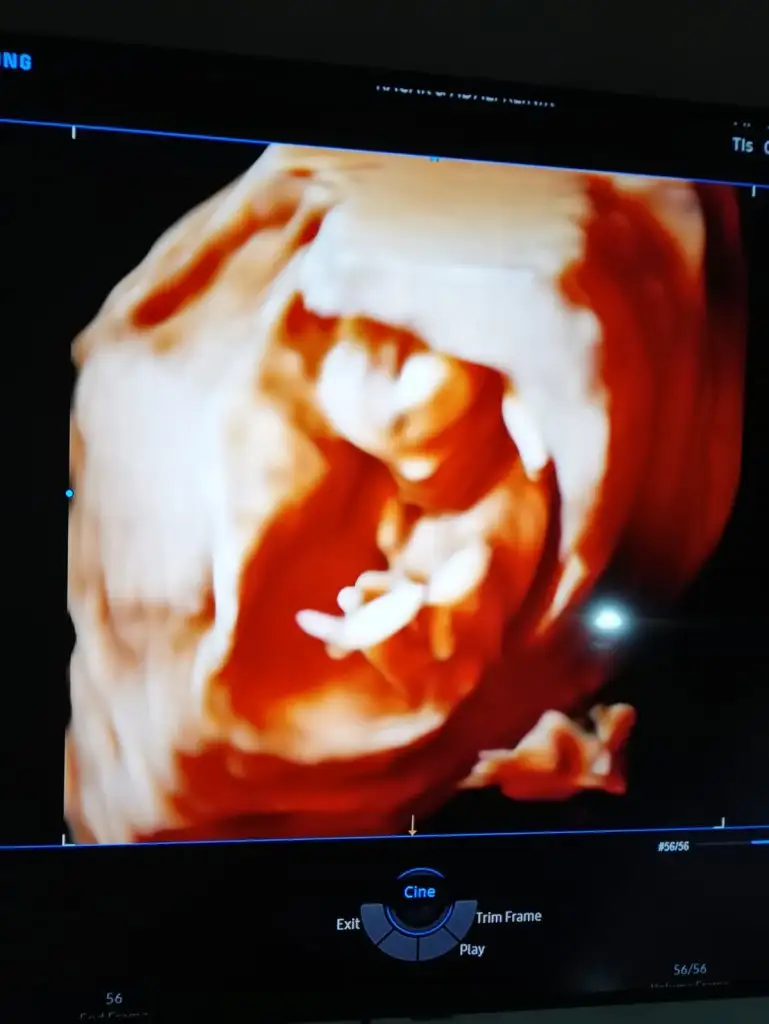

dr soylemeden siz gorun genital nub teorisi ( bebegin cinsiyeti)

Bu gördüğüm nub ise hafif dik görünüyor 😬

Aynen hayırlı saglıklı gönlündeki olur inşallah eminde olamadım tam dik değil hafif dik gibi 😬